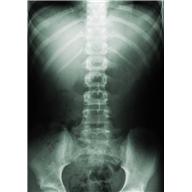

Exercises For Low Back Pain

Flexibility and strengthening exercises help to reduce the pain and disability of chronic nonspecific low back pain.  Hoping to find a simple straightforward program to suggest to you, I reviewed “Exercise-based therapy for low back pain” at UpToDate.com.

• low back pain is the most common musculoskeletal disorder worldwide

• 85% of us experience low back pain at some point

• in the U.S., yearly total cost of low back pain exceeds $100 billion

The UpToDate folks suggest a combination of core strengthening (especially abdominal and trunk extension), directional preference (e.g., McKenzie method), general physical fitness, flexion and extension movements, aerobics, and functional restoration programs.  Some studies found benefit with Alexander technique, yoga, Pilates, and tai chi.